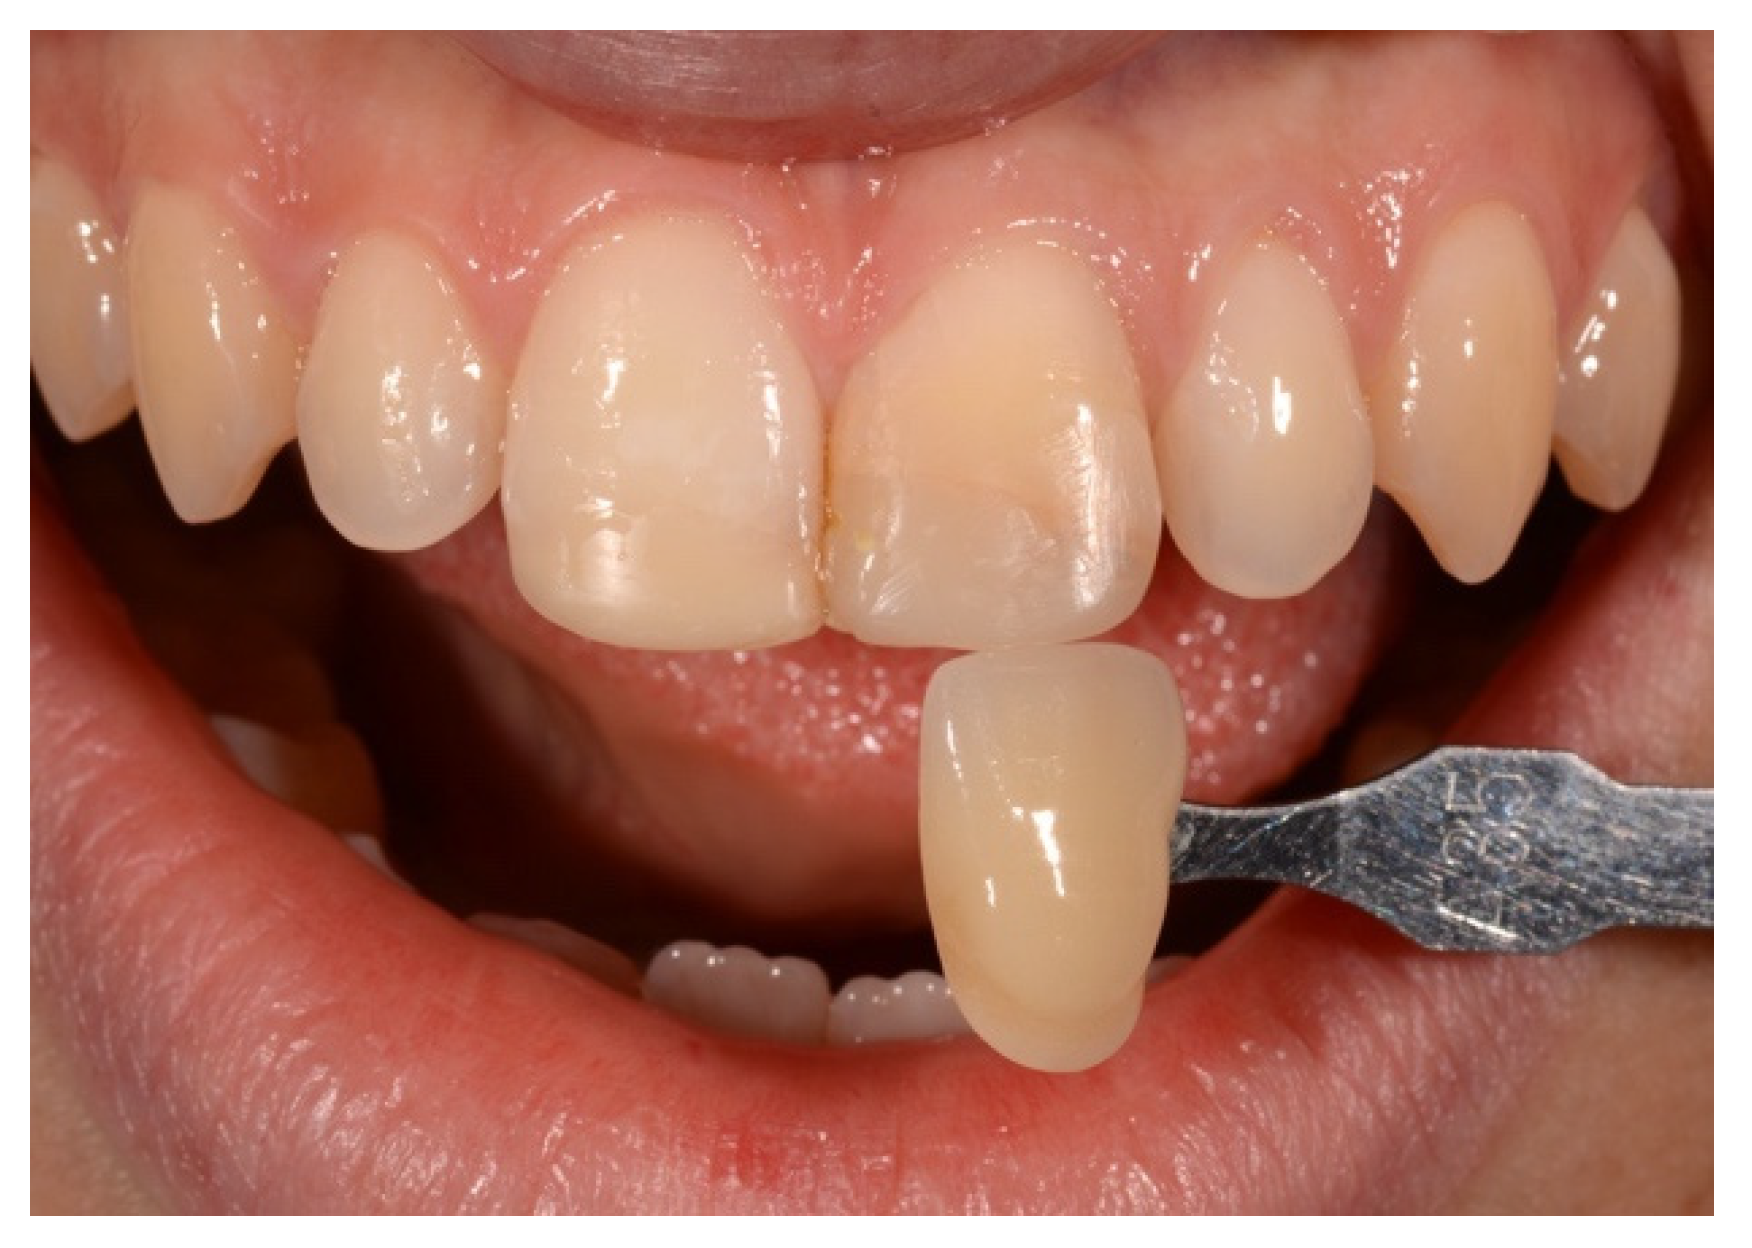

2. Case Presentation